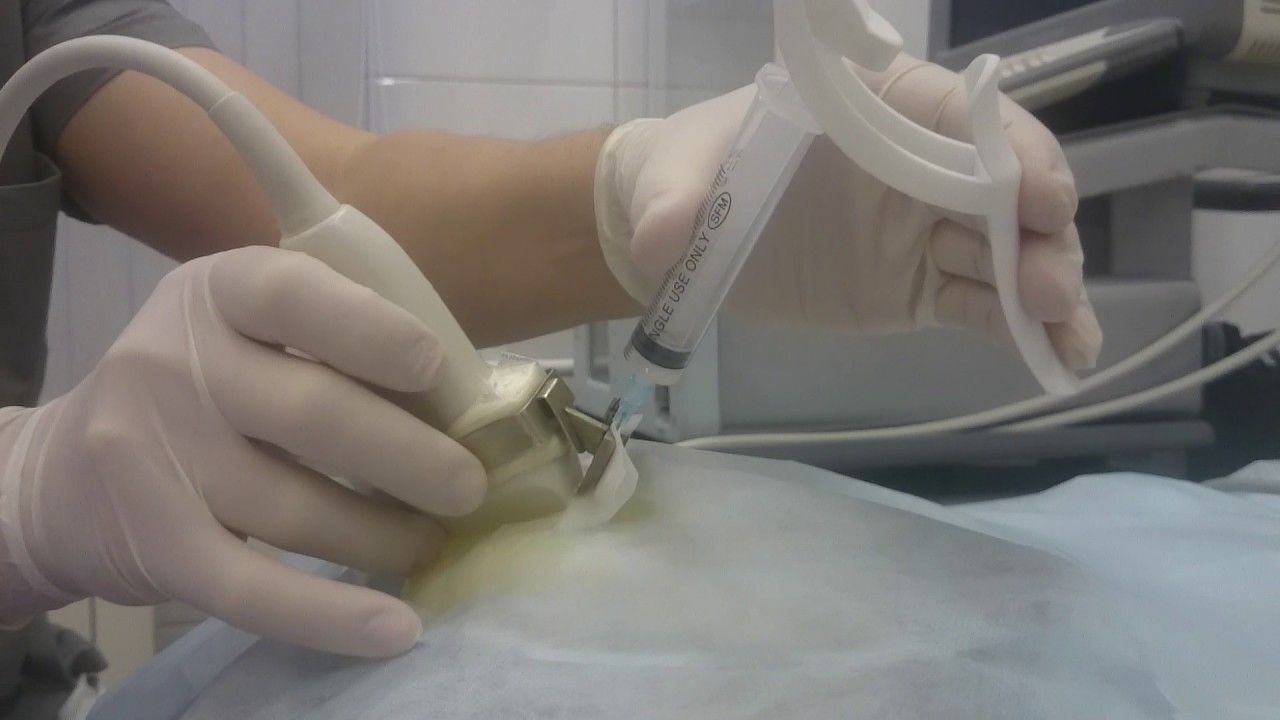

Обследование также включает тонкоигольную аспирационную биопсию. Метод помогает отличить кистоз от фиброаденомы. Эти два заболевания имеют одинаковую симптоматику. С помощью пункции определяются цвет и характер жидкости в кисте, а также образование гнойных инфильтратов. В особенных случаях проводится цистологическое исследование биоматериала, которое опровергает или подтверждает онкологию.

Однако чаще всего при наличии гнойного процесса кисты молочной железы врачам приходится прибегать к оперативному вмешательству. Эта процедура обычно проводится в условиях стационара под общей анестезией.

- При воспалении, ограниченном объёмом кисты, специалисты прибегают к её пунктированию, аспирации гнойного содержимого и введению в просвет кисты лекарственных препаратов. Подобная манипуляция не занимает много времени и не требует длительного пребывания в стационаре.

- Ультразвуковое исследование.

- Тонкоигольная аспирационная биопсия кистозного образования – один из наиболее информативных методов диагностики заболевания, так как симптоматика кистоза достаточно созвучна с проявлениями фиброаденомы. Диагностика обоих этих заболеваний несколько проблематична. В свете различных методик лечения, установить правильную причину патологии просто необходимо. Данную пункцию медики относят как к диагностическим методам исследования, так и к лечебным процедурам молочной железы. Ведь констатировать кисту уже можно на стадии пунктирования, оценившись с объемом «откачанной» жидкости. Если получено жидкости больше 1 мл, констатируют наличие кисты в груди женщины.

- Гормональное лечение с помощью гестагенов и проведения пункции полости кисты. Содержимое внутри полости откачивается, применяя специальную иглу, и направляется на цитологическое исследование. В полость кисты закачиваются препараты, которые стимулируют слипание её стенок.